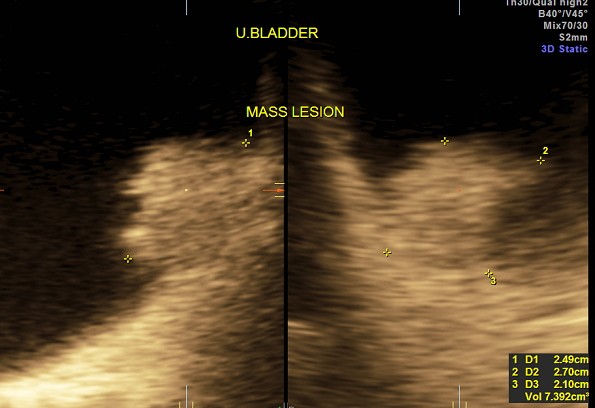

the next is a post void picture showing the mass

this patient underwent surgery and histopathology proved the diagnosis of bladder carcinoma and he is doing well now.

the next is a 3 d reconstruction , which shows the prominent median lobe prominence adjacent to the mass.